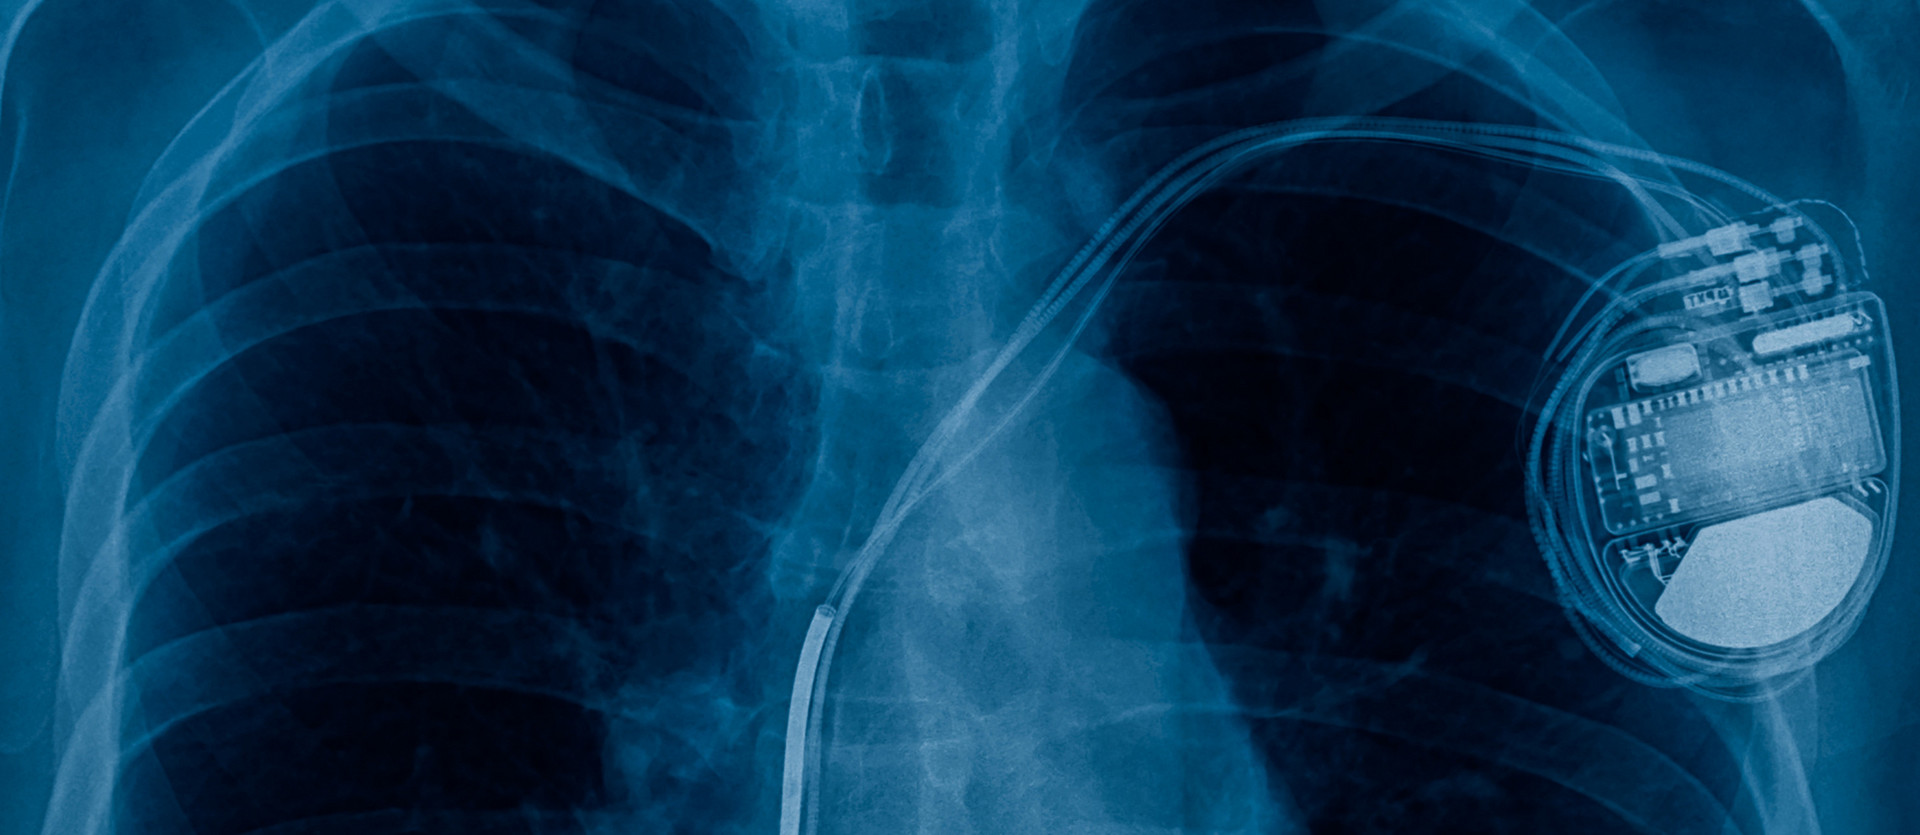

HERZSCHRITTACHER

Bei jedem dritten Betroffenen pumpen die beiden Herzkammern nicht mehr synchron (gleichzeitig). Systeme zur kardialen Resynchronisation, von Kardiologen als CRT-Systeme bezeichnet, sind Schrittmachersysteme, die mit einer dritten Elektrode ausgestattet sind. Das Gerät umfasst somit sämtliche Funktionen eines normalen Herzschrittmachers, bietet ergänzend jedoch die Möglichkeit, die rechte und linke Herzkammer synchron zu stimulieren.

Ziel einer kardialen Resynchronisationstherapie ist, die Kontraktion der beiden Herzkammern aufeinander abzustimmen, zu resynchronisieren. Dies führt bei einer Herzschwäche zu einer verbesserten Überlebenschance und zu einer Steigerung der Leistungsfähigkeit. CRT-Systeme werden bevorzugt Patienten empfohlen, bei denen mittels EKG ein sogenannter Linksschenkelblock festgestellt wurde. Bei Herzschwäche-Patienten mit einem zu langsamen Herzschlag, von Kardiologen Bradykardie genannt, kann die Implantation eines konventionellen Herzschrittmachers eine erfolgreiche Therapiemethode sein.